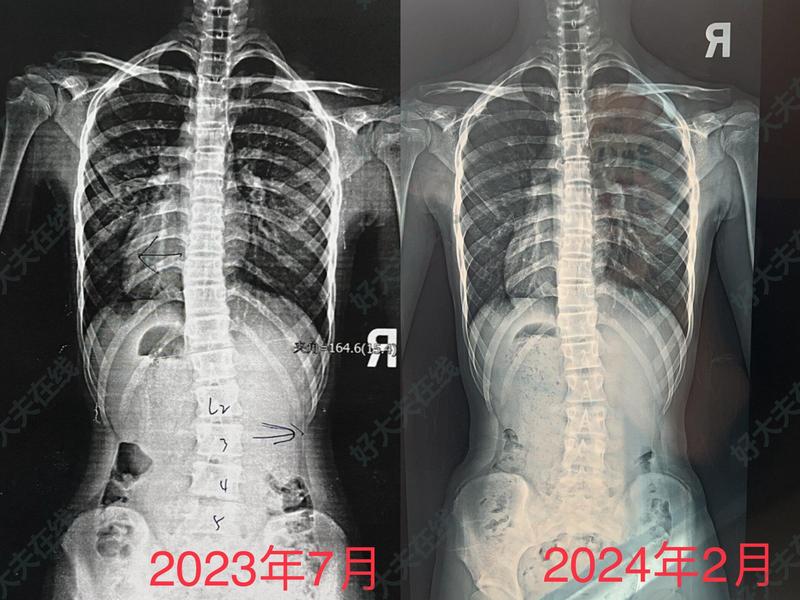

治療前患者女14歲,因脊柱側(cè)彎來診。查脊柱不正,尤以胸腰段明顯,高低肩明顯。治療中手法正骨整脊治療,一周一次治療近半年,可以看到脊柱側(cè)彎明顯好轉(zhuǎn)。治療后治療后14天身高長高了2厘米,現(xiàn)仍需繼續(xù)堅(jiān)持治療,注意坐姿站姿臥姿,臥板床休息。